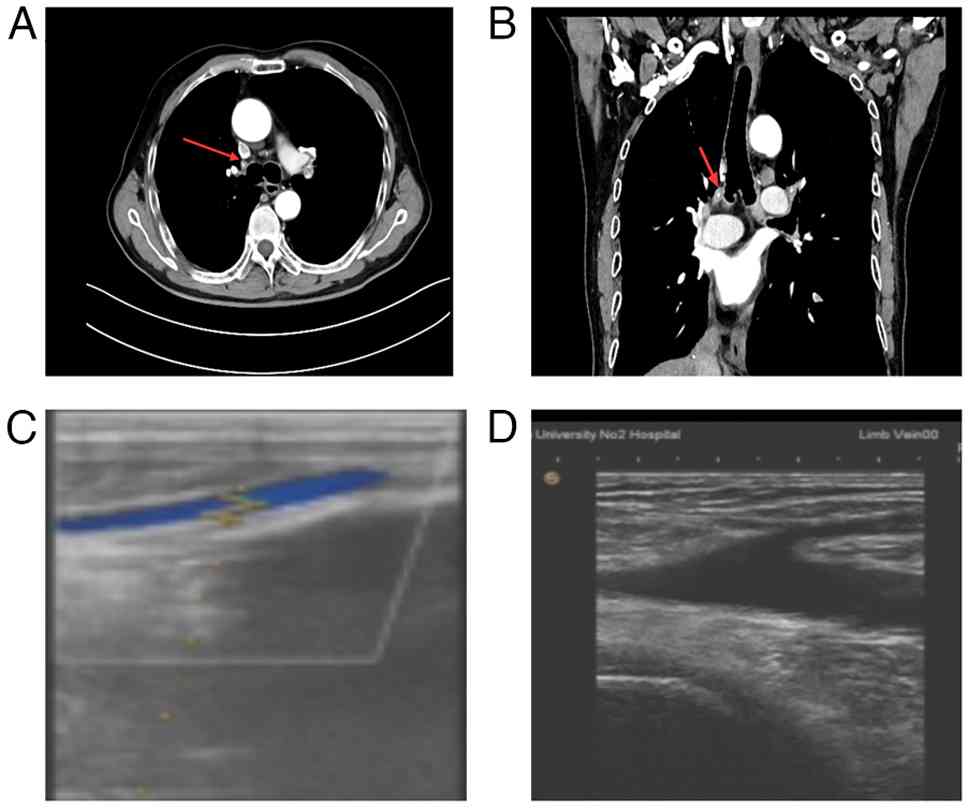

The plan post-chemotherapy was to perform enhanced chest and abdominal CT scans every 3 months for 1 year to assess the patient's condition. A CT scan at 3 months post-chemotherapy revealed a pulmonary artery embolism in the right upper lobe, and color Doppler ultrasound of the lower extremities revealed a thrombus in the right calf muscle vein (Fig. 3). Oral rivaroxaban (20 mg once daily) was administered for anticoagulant therapy. After 3 months of anticoagulation therapy, the pulmonary embolism had resolved.

Imaging findings of pulmonary embolism

and lower extremity thrombosis. (A) CT scan performed at 3 months

post-chemotherapy (axial view) revealing a pulmonary artery

embolism in the right upper lobe (indicated by the arrow). (B) CT

scan (coronal view) confirming the pulmonary artery embolism in the

right upper lobe. (C) Color Doppler ultrasound of the lower

extremities revealing a thrombus in the right calf muscle vein. (D)

Color Doppler ultrasound (cross-sectional view) further

demonstrating the thrombus within the right calf muscle vein.

Figure 3.

Imaging findings of pulmonary embolism and lower extremity thrombosis. (A) CT scan performed at 3 months post-chemotherapy (axial view) revealing a pulmonary artery embolism in the right upper lobe (indicated by the arrow). (B) CT scan (coronal view) confirming the pulmonary artery embolism in the right upper lobe. (C) Color Doppler ultrasound of the lower extremities revealing a thrombus in the right calf muscle vein. (D) Color Doppler ultrasound (cross-sectional view) further demonstrating the thrombus within the right calf muscle vein.